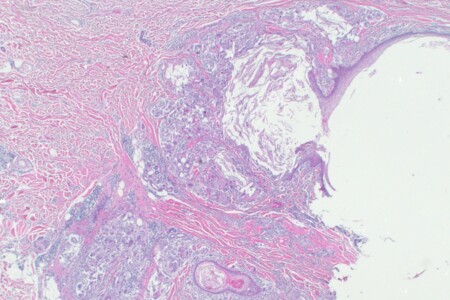

Abscesy neboli hlízy jsou ohraničená zánětlivá ložiska, která se mohou tvořit kdekoliv uvnitř těla nebo na jeho povrchu. Jejich rozměry se různí od drobných puchýřků a vřídků na kůži nebo při vlasových koříncích až po závažnější abscesy zubních lůžek nebo abscesy vnitřních orgánů, například při zánětu slepého střeva (apendixu).